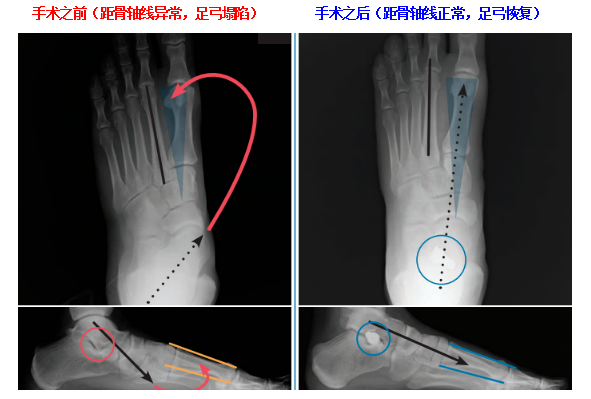

手術前后的影像學改變